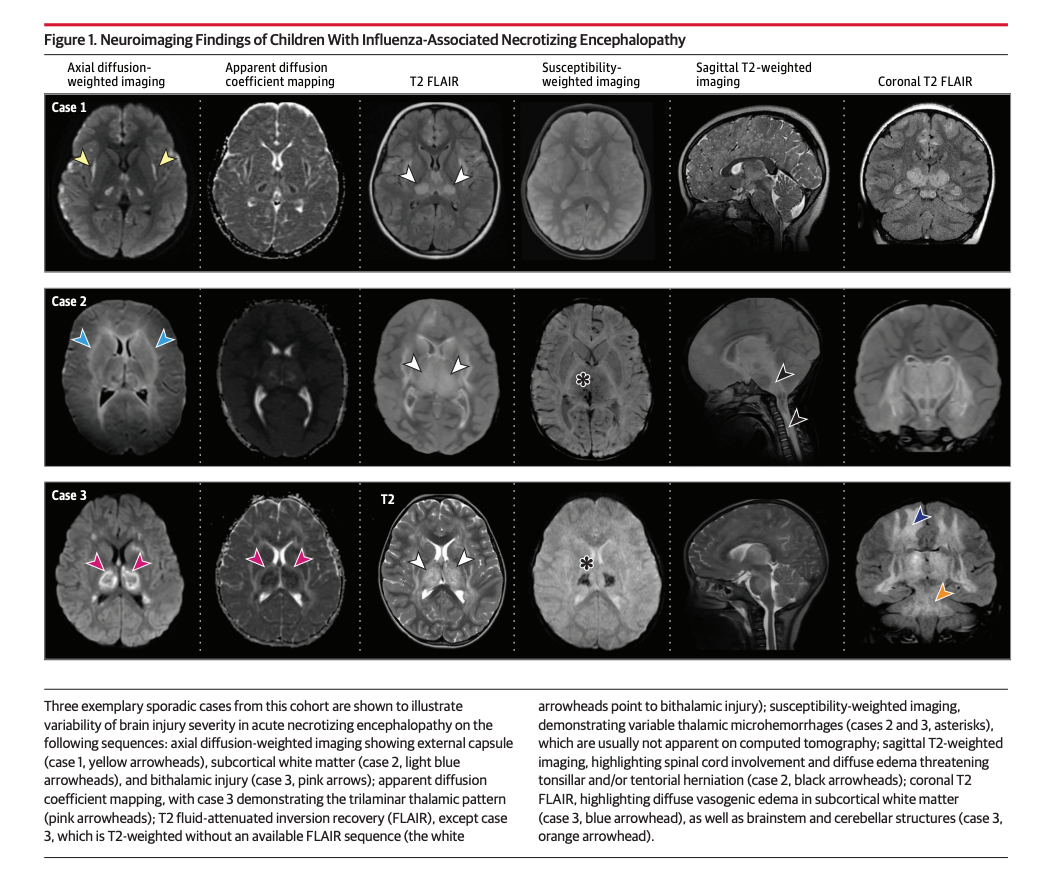

Acute necrotizing encephalopathy is a severe neurologic condition that can result in brain damage and swelling following a viral infection -- and particularly during influenza. Over this past flu season, researchers said pediatric doctors reported an increased number of children with the condition tied to flu.

Doctors have identified 41 cases of acute necrotizing encephalopathy in children at 23 hospitals over the past two flu seasons. Most of those children had been healthy, with no significant medical history, before contracting the flu.

Of those children, 11 died within three days of the complication’s onset. For the 30 who survived, 63 percent had moderate to severe disability 90 days after diagnosis, including problems walking, eating and seizures.